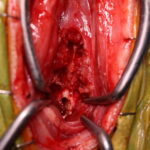

体の何処かを痛がるとの事でダックスさんがかかりつけ医を受診したところ、椎間板ヘルニアではないか?との頃で精査のため来院されました。エックス線検査とMRIでC2~C3に脊髄圧迫病変が確認されました。Ventral Slotで脊柱管内に逸脱した椎間板物質を摘除しました。速やかに除痛効果が現れています。